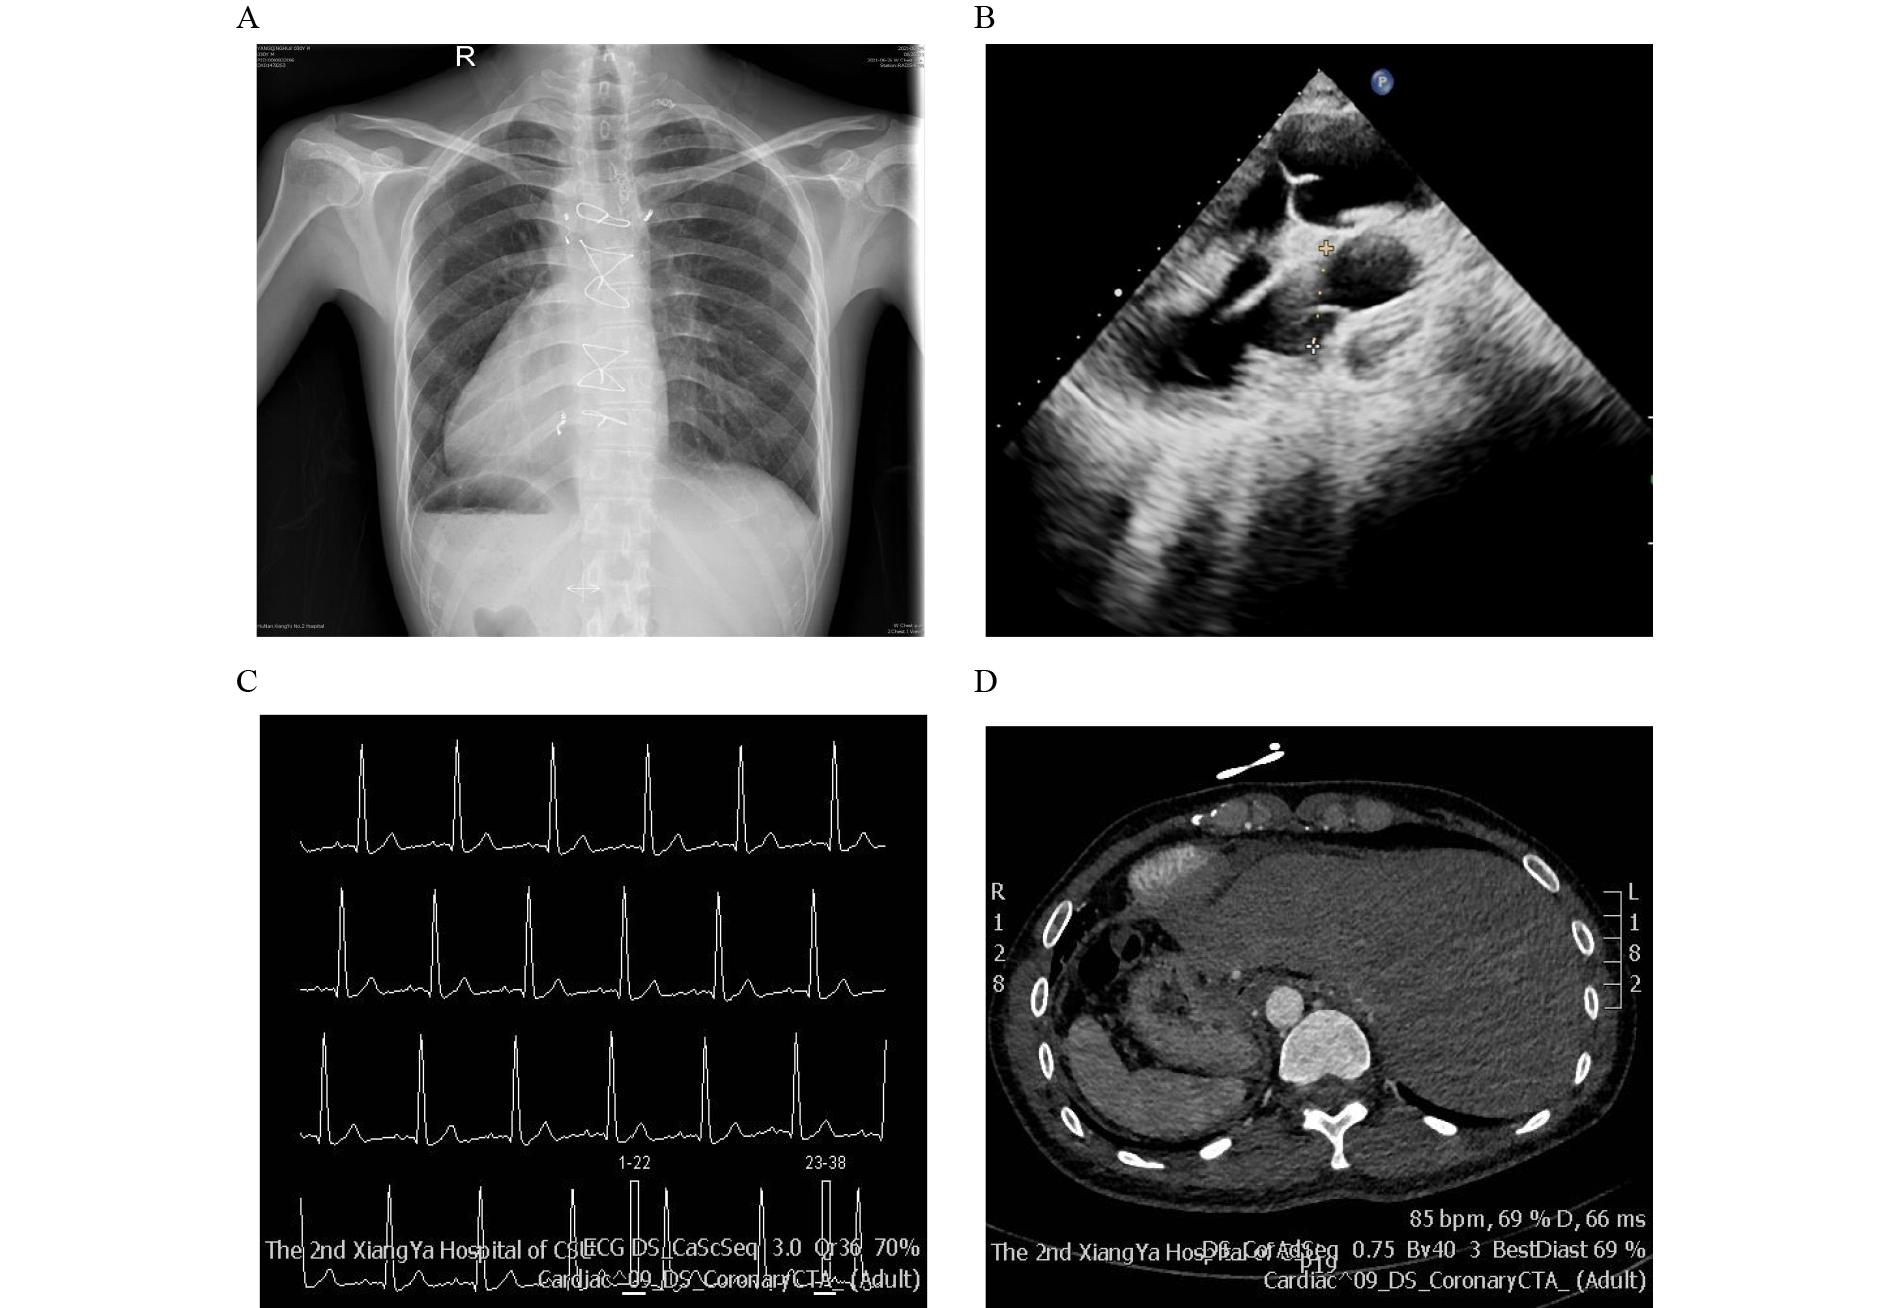

Zhuangzhuang Yuan, Xin Zhu, Xiaohui Xie, Chenyu Wang, Heng Gu, Junlin Yang, Liangliang Fan, Rong Xiang, Yifeng Yang, Zhiping Tan

The establishment of left–right asymmetry is a fundamental process in animal development. Interference with this process leads to a range of disorders collectively known as laterality defects, which manifest as abnormal arrangements of visceral organs. Among patients with laterality defects, congenital heart diseases (CHD) are prevalent. Through multiple model organisms, extant research has established that myosin-Id (MYO1D) deficiency causes laterality defects. This study investigated over a hundred cases and identified a novel biallelic variant of MYO1D (NM_015194: c.1531G>A; p.D511N) in a consanguineous family with complex CHD and laterality defects. Further examination of the proband revealed asthenoteratozoospermia and shortened sperm. Afterward, the effects of the D511N variant and another known MYO1D variant (NM_015194: c.2293C>T; p.P765S) were assessed. The assessment showed that both enhance the interaction with β-actin and SPAG6. Overall, this study revealed the genetic heterogeneity of this rare disease and found that MYO1D variants are correlated with laterality defects and CHD in humans. Furthermore, this research established a connection between sperm defects and MYO1D variants. It offers guidance for exploring infertility and reproductive health concerns. The findings provide a critical basis for advancing personalized medicine and genetic counseling.